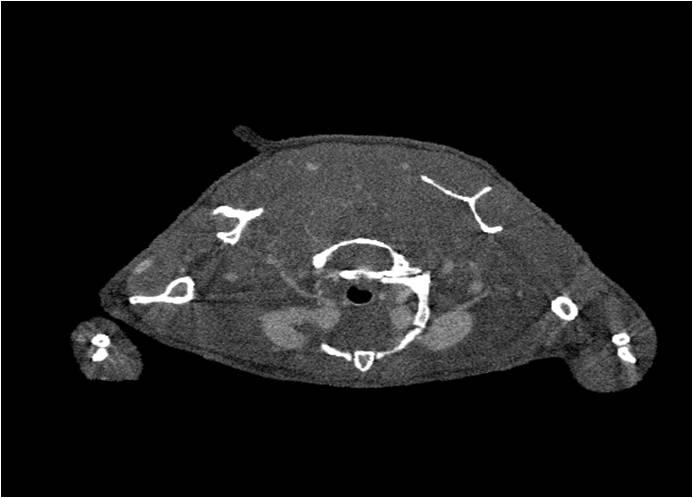

檢測案例

小鼠股骨

超高分辨率模式下像素大小為9μm。

A軸向和矢狀面顯示小鼠股骨結構。

B用鈦材料植入的穿過骨頭的冠狀切片

腫瘤血管生成

肺轉移

小鼠模式,22.5μm像素

正常

8天 14天

無造影劑注入 造影劑注入